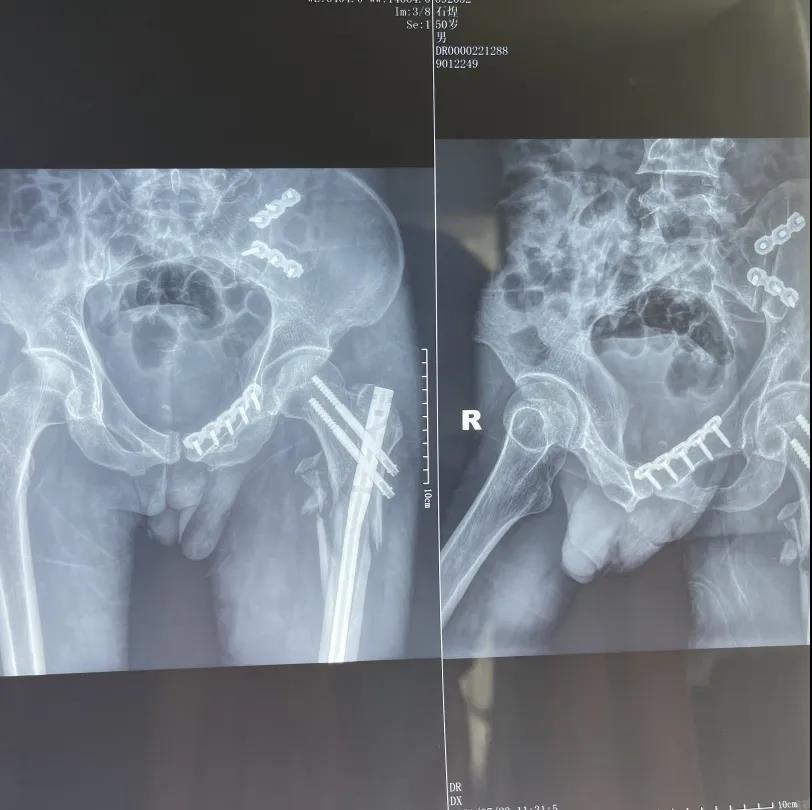

▲术后影像学资料

分三期手术,分别在全麻下行左股骨粗隆间粉碎性骨折及粗隆下骨折有限切开复位内固定术,左骼骨骨折合并骶骼关节分离切开复位内固定术,下颌骨粉碎性骨折切开复位内固定术(术后恢复了咬合关系,患者可以进半流质饮食),左尺骨鹰嘴粉碎性骨折切开复位内固定术,左跟骨粉碎性骨折切开复位活动术。手术均获得成功,病人骨折达到临床愈合,肢体功能恢复良好,无感觉障碍及并发症,伤口愈合良好。